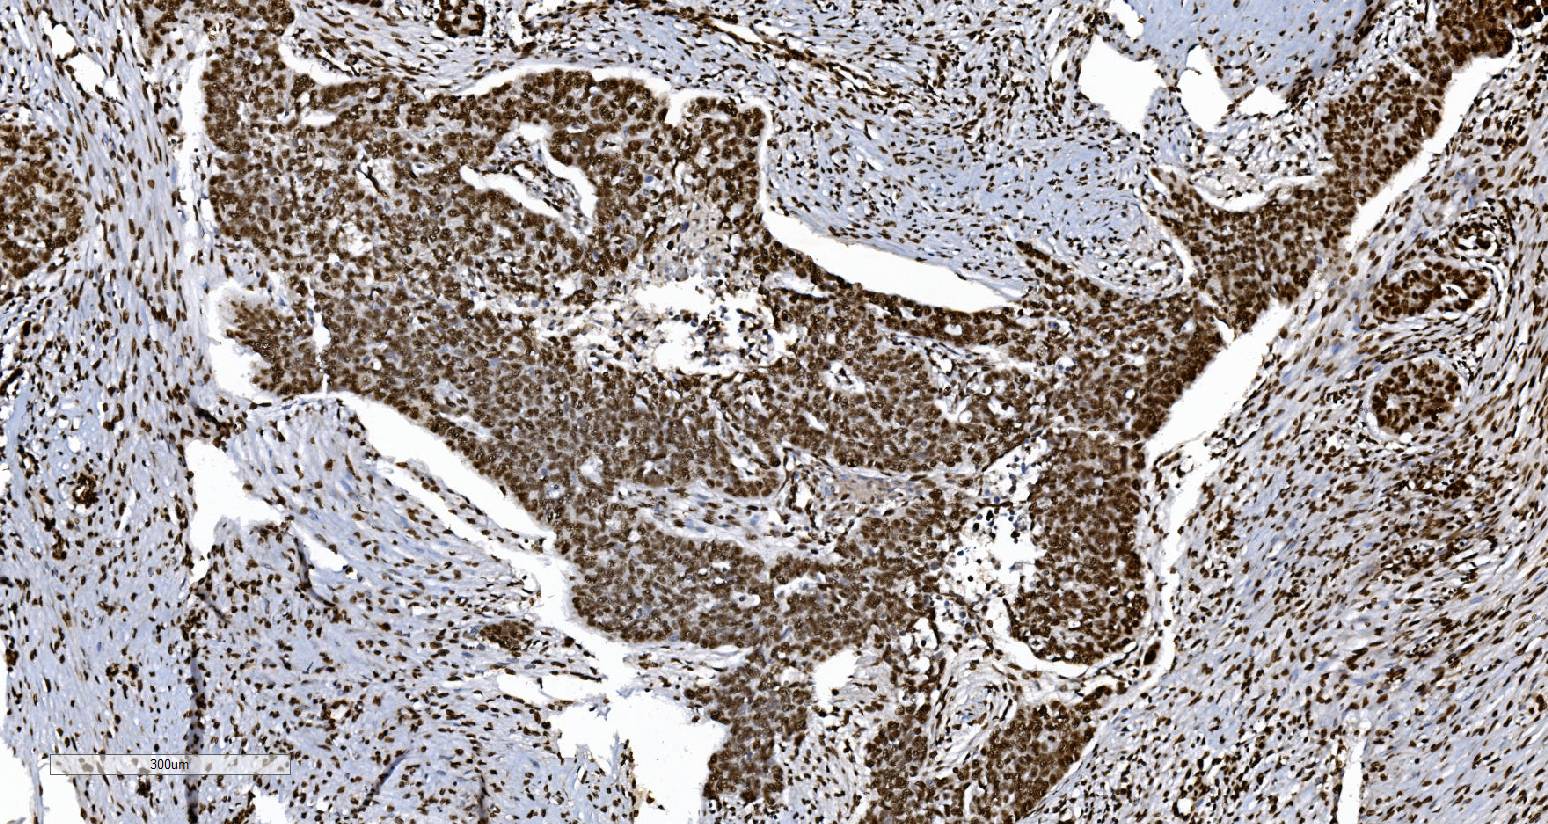

IHC analysis of KU70/XRCC6 using anti-KU70/XRCC6 antibody (M01732-4).

KU70/XRCC6 was detected in a paraffin-embedded section of human renal clear cell carcinoma tissue. Biotinylated goat anti-mouse IgG was used as secondary antibody. The tissue section was incubated with mouse anti-KU70/XRCC6 Antibody (M01732-4) at a dilution of 1:200 and developed using Strepavidin-Biotin-Complex (SABC) (Catalog # SA1021) with DAB (Catalog # AR1027) as the chromogen.